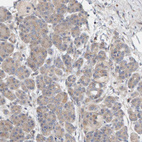

Immunohistochemistry analysis in human lymph node and pancreas tissues using HPA021669 antibody. Corresponding CCM2 RNA-seq data are presented for the same tissues.